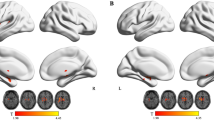

The control group exhibited significant activation in the left medial frontal gyrus, bilateral middle, inferior and superior frontal gyri, bilateral inferior parietal lobules extending to the precuneus and superior parietal lobule, the right middle temporal gyrus, and the right cerebellum posterior lobe in “2-back” minus “1-back” contrast ( Table 2 and Figure 3 ). The PMNE group exhibited similar but weaker activation in the right medial frontal gyrus, bilateral middle and inferior frontal gyri, bilateral inferior parietal lobules, and the right superior parietal lobule ( Table 2 and Figure 3 ).The PMNE group exhibited significantly decreased activation in the right precentral gyrus, and the right inferior parietal lobule extending to the postcentral gyrus compared with controls ( Table 2 and Figure 3 ).

Significant activation and deactivation between 2-back vs. 1-back during low and high difficulty working memory tasks. Red represents positive activation, whereas blue represents negative activation. P < 0.05 with AlphaSim corrected (combined height threshold of P < 0.001 and a minimum cluster size of 49 voxels).

Task-related default mode network. Control children exhibited significantly reduced activation in the left anterior cingulate extending to the left medial frontal gyrus and the left anterior cingulate cortex during the n-back task compared with PMNE children ( Table 3 , Figures 2 and 3 ). Children with PMNE exhibited more n-back-related default mode network negative activation ( Table 3 , Figures 2 and 3 ) in the right medial frontal gyrus, left precuneus, left middle and posterior cingulate gyri, bilateral anterior cingulate cortex, left middle temporal gyrus, right parahippocampal gyrus, right precentral gyrus, and left cuneus extending to the lingual gyrus and insula cortex compared with controls.

Both groups of children exhibited activation of the fronto-parietal network during performance of the n-back task. In support of our hypothesis, different patterns of activity were observed in the working memory network in the PMNE group compared with controls. Children with PMNE exhibited more areas of activation during performance of the 1-back vs. 0-back tasks and exhibited less areas of activation during performance of the 2-back vs. 0-back tasks compared with healthy children ( Figure 2 ). Furthermore, the PMNE group exhibited significantly decreased activation in the right precentral gyrus and the right inferior parietal lobule extending to postcentral gyrus when the 2-back and 1-back conditions were compared directly ( Figure 3 ). These results suggest that children with PMNE tend to engage more brain areas during low difficulty working memory tasks and less brain areas during high difficulty working memory tasks compared to healthy children.

The PMNE group exhibited significantly decreased activation in the right precentral gyrus and the right inferior parietal lobule extending to the postcentral gyrus compared with the controls for the “2-back” minus “1-back” contrast. This result may suggest PMNE children decrease sensorimotor cortex activation to pay more attention to the task. The group difference occurred because of deactivation of the DMN in PMNE children. Children with PMNE had significantly more deactivation in the DMN compared to healthy controls. The DMN typically consists of the medial prefrontal cortex, posterior cingulate/precuneus, inferior parietal lobe, lateral temporal lobes, and hippocampal formation (21,22). The DMN is characterized by high activity when the mind is not engaged in specific behavioral tasks and low activity during focused attention on the external environment (23). Deactivation in the DMN reflects the allocation of cerebral resources to support task performance. The DMN tends to reduce activation when attention is focused on a particular task, and it tends to increase activation when attention is relaxed (21,22). Children with PMNE exhibited more deactivation in the DMN, which suggests that they paid more attention and tried their best to perform the n-back task. Anticevic et al. (23) demonstrated that DMN suppression was closely related to goal-directed cognition, possibly by a reduction in goal-irrelevant functions (e.g., mind-wandering). Previous studies demonstrated that greater DMN deactivation is associated with more successful performance in goal-directed cognitive tasks (24,25,26). Similarly, defective deactivation of DMN regions is associated with worse behavioral performance in several conditions associated with cognitive impairment (27,28,29). Children with PMNE exhibited significant deactivation during low and high difficulty working memory tasks (0-back vs. 1-back and 0-back vs. 2-back), and healthy children exhibited a few areas of deactivation during high difficulty working memory tasks (0-back vs. 2-back). McKiernan et al. (30) found that task-induced deactivation of the default mode network increased with task difficulty. Therefore, the low difficulty working memory task was not easy for PMNE children. The longer RT during 1-back working memory in children with PMNE compared with the control group also supports this hypothesis. The additional deactivation suggests that children with PMNE tend to compensate with greater DMN deactivation to sustain normal working memory function.